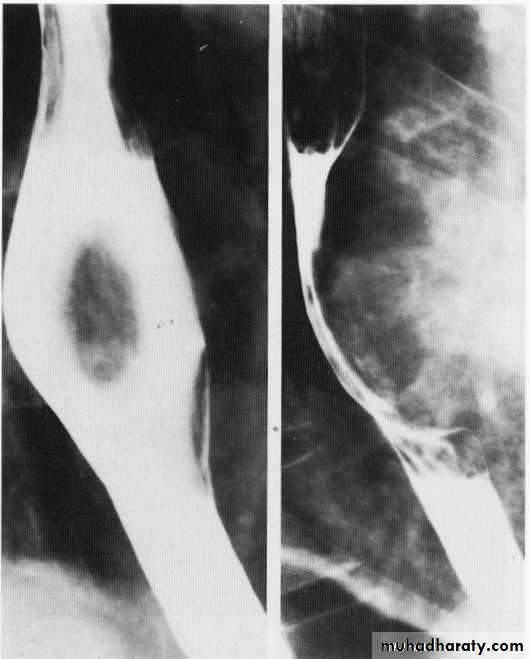

Leiomyoma Ba swallow

Leiomyoma EUS